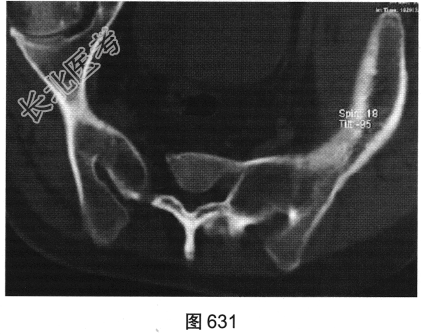

- 多项选择题2.[提示]患者行脊椎及骶髂关节CT检查,见图629~图631。该患者CT图片有哪些阳性征象( )

D、椎旁韧带骨化

E、胸腰段后凸畸形

F、双侧骶髂关节及脊椎椎小关节间隙消失

G、竹节椎